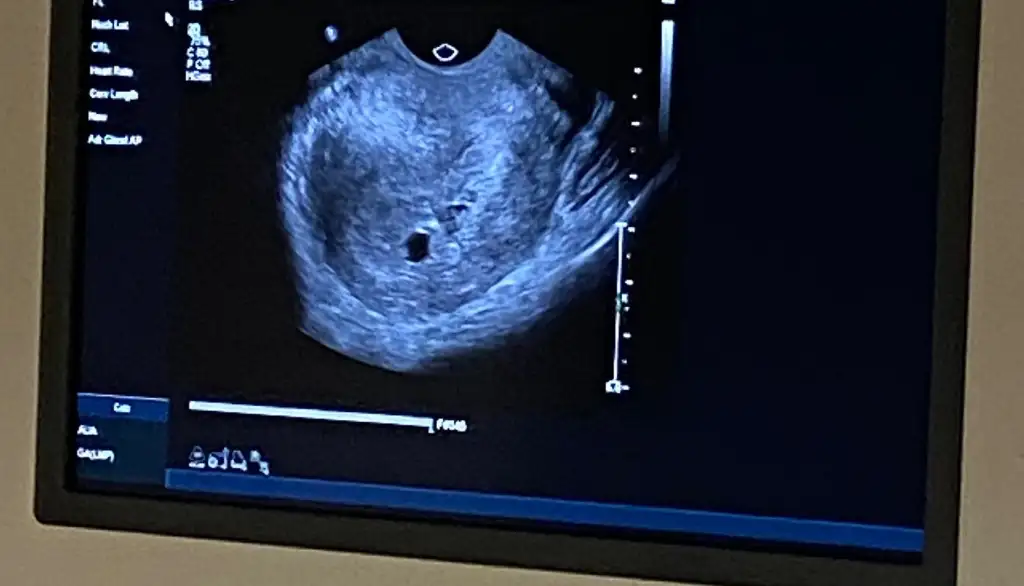

Selamünaleyküm canm öncelikle hiç korkma bisi olmuyor o bende de vardı bisi olmuyor yani 12. Haftada falan kayboldu kese büyüdükçe kayboluyor bana hatta progestan vermişti doktorum o bana yan etki yaptı bıraktım ama yine de kayboldu 5 gün kullanabildim sadece ama merak etme gidiyor sadece dikkat et9 haftalık hamileyim 5.haftanın sonunda bebeği ve kalp atışını görmüştük o gün kanama alanı tespit edildi doktor progestan fitil başlattı bugün kontrolüm vardı kanama alanı hala duruyor bebek sağlıklı görünüyor çok şükür doktor büyümemişte küçülmemişte ama yok olmadığı sürece her zaman riskli dedi benim dışarıdan bir kanamam lekelenmem olmadı şükür ki ama sürekli risk denmesi çok tedirgin ediyor bu süreci yaşayanlar varsa bilgi almak isterim 12. 16.haftaya kadar kaybolabilir o zamana kadar risk var diyeceğim dedi doktor ama benim düşüncem bir şey olmaz diyor ultrason fotoğrafını da ekliyorum

Benim 4 gebeliğimde de vardı kan sulandırıcı iğne ve ilaç kullanıyorsanız birinin kesilmesi gerek9 haftalık hamileyim 5.haftanın sonunda bebeği ve kalp atışını görmüştük o gün kanama alanı tespit edildi doktor progestan fitil başlattı bugün kontrolüm vardı kanama alanı hala duruyor bebek sağlıklı görünüyor çok şükür doktor büyümemişte küçülmemişte ama yok olmadığı sürece her zaman riskli dedi benim dışarıdan bir kanamam lekelenmem olmadı şükür ki ama sürekli risk denmesi çok tedirgin ediyor bu süreci yaşayanlar varsa bilgi almak isterim 12. 16.haftaya kadar kaybolabilir o zamana kadar risk var diyeceğim dedi doktor ama benim düşüncem bir şey olmaz diyor ultrason fotoğrafını da ekliyorum

Benim de kanama alanı var şuan bebek 5 haftalık. Kese göründü ama yolk sac görünmedi9 haftalık hamileyim 5.haftanın sonunda bebeği ve kalp atışını görmüştük o gün kanama alanı tespit edildi doktor progestan fitil başlattı bugün kontrolüm vardı kanama alanı hala duruyor bebek sağlıklı görünüyor çok şükür doktor büyümemişte küçülmemişte ama yok olmadığı sürece her zaman riskli dedi benim dışarıdan bir kanamam lekelenmem olmadı şükür ki ama sürekli risk denmesi çok tedirgin ediyor bu süreci yaşayanlar varsa bilgi almak isterim 12. 16.haftaya kadar kaybolabilir o zamana kadar risk var diyeceğim dedi doktor ama benim düşüncem bir şey olmaz diyor ultrason fotoğrafını da ekliyorum